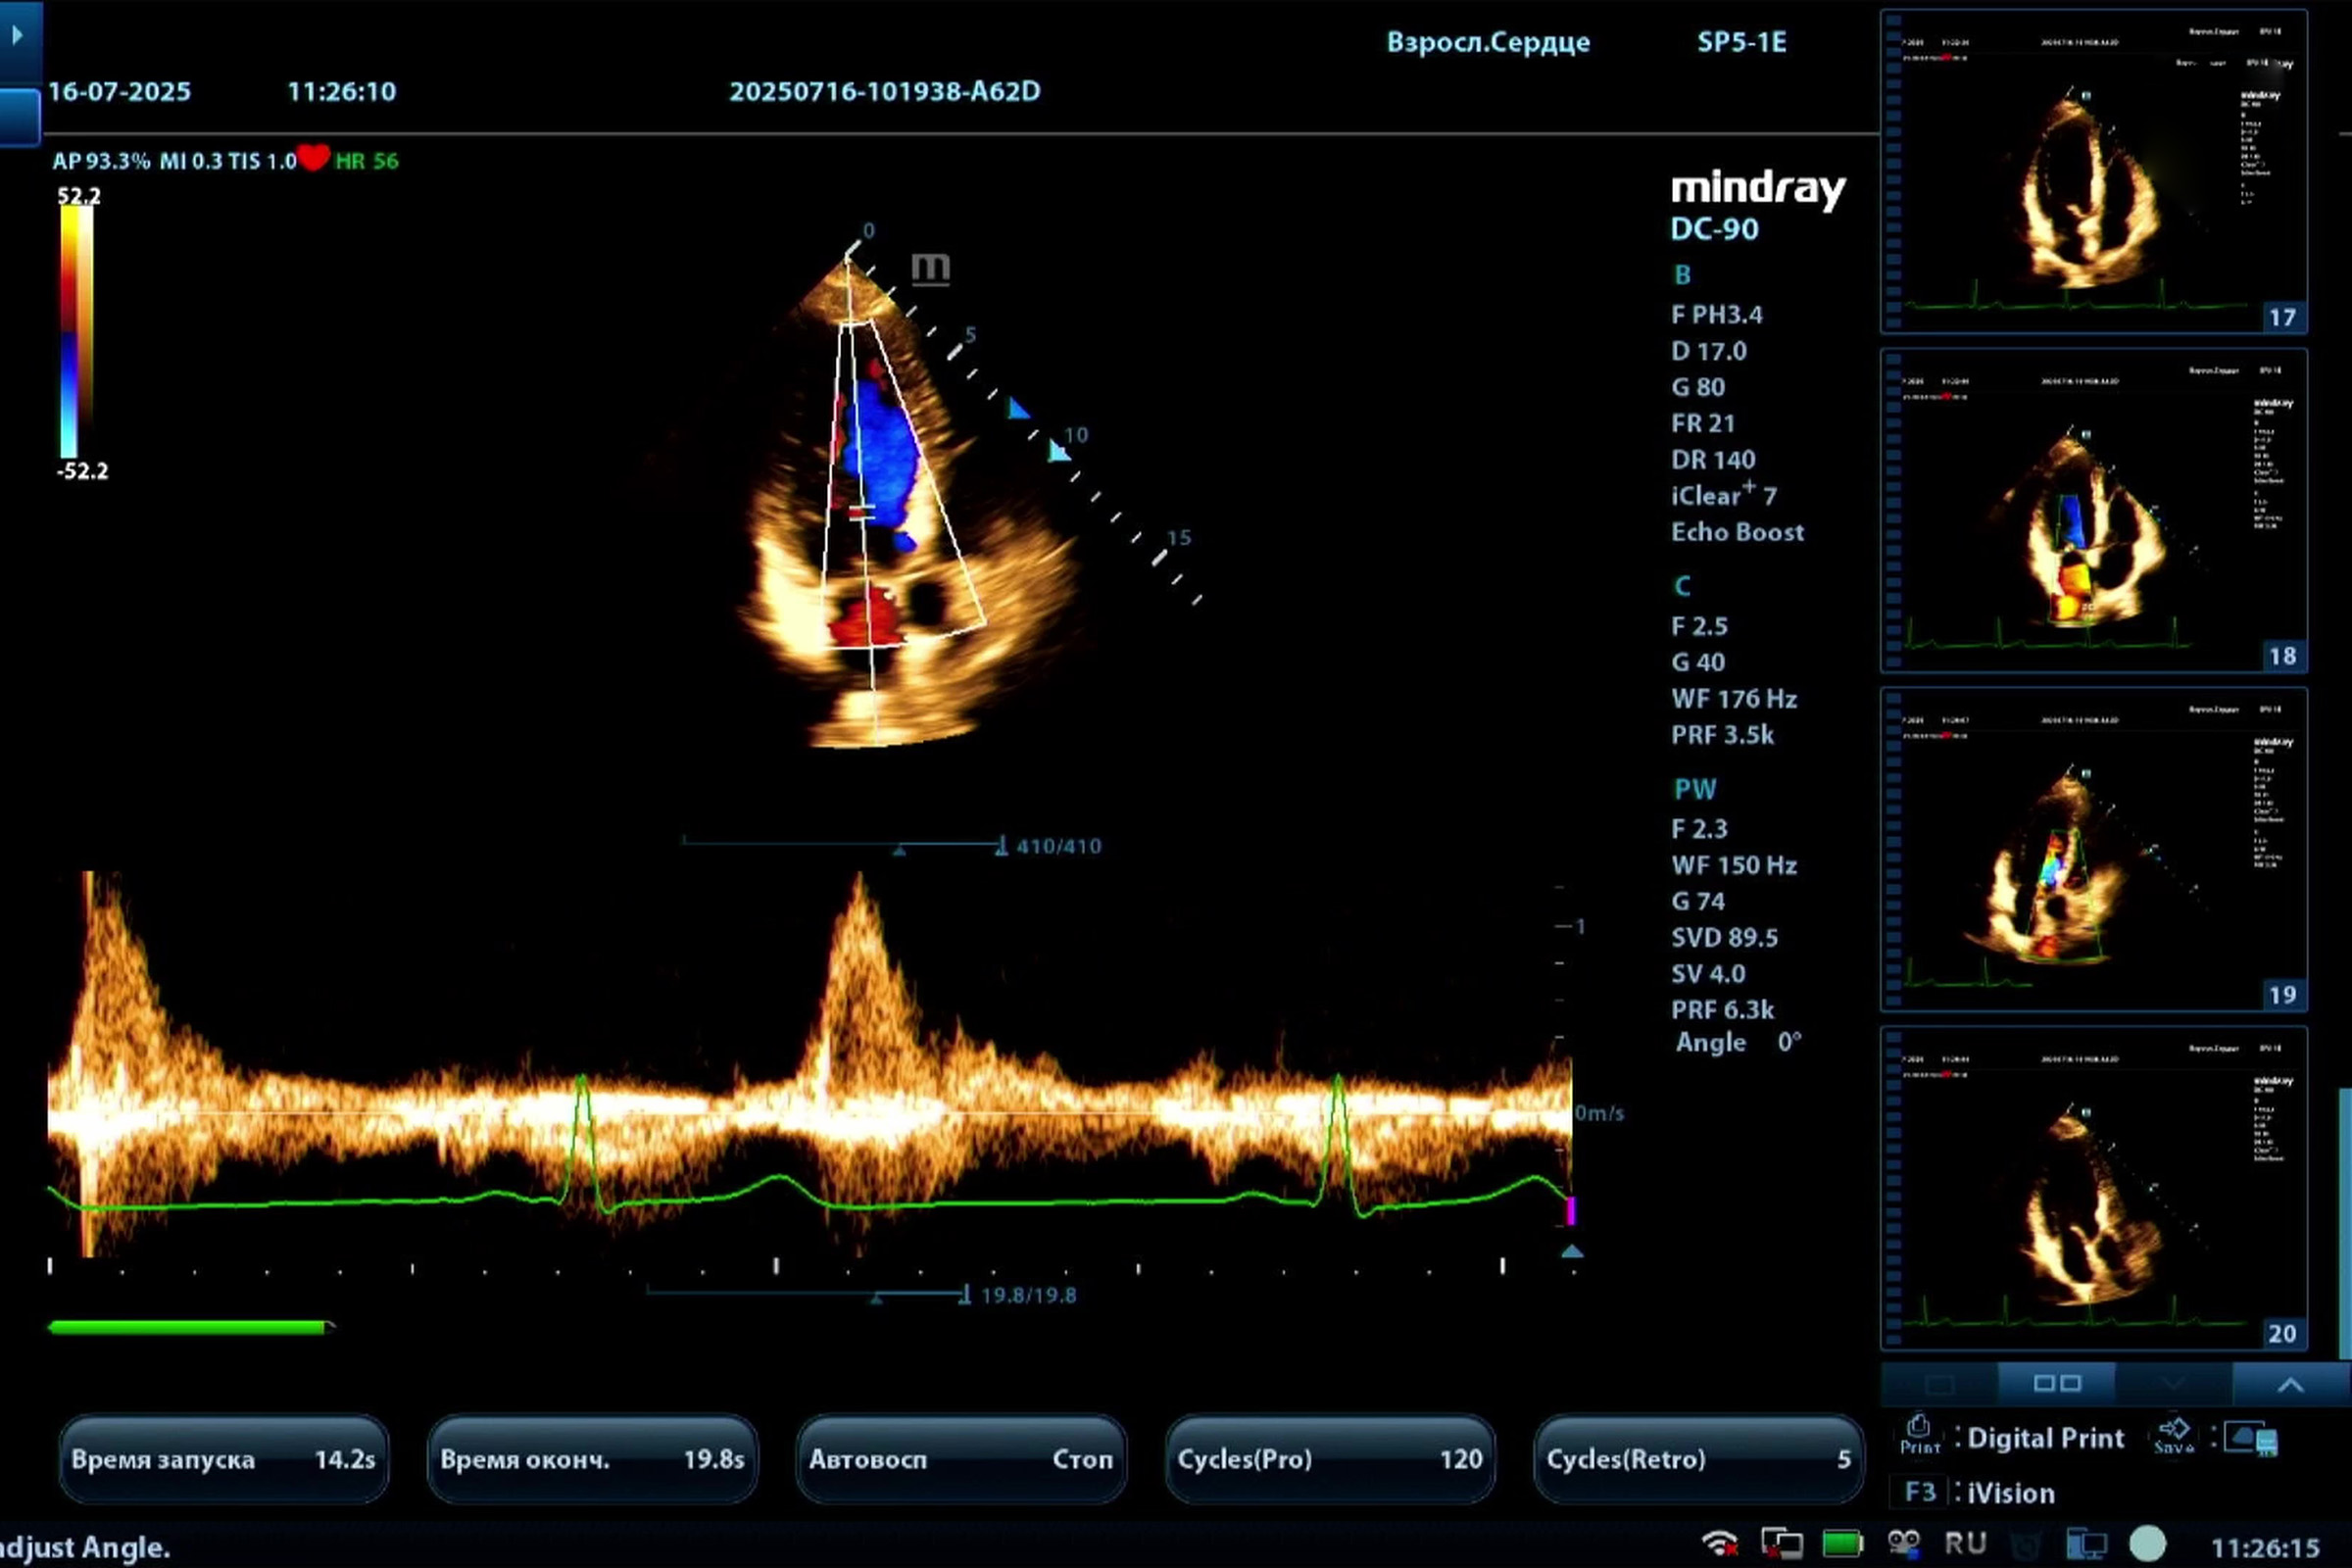

Медицинское оборудование для ультразвуковой диагностики